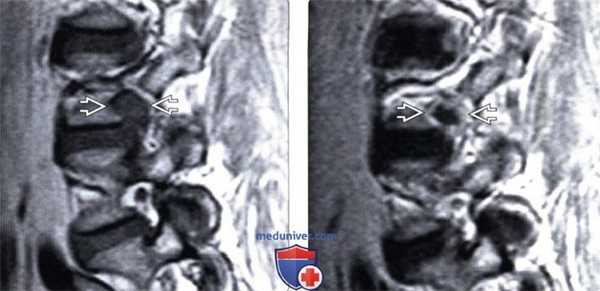

(Слева) Т1-ВИ, сагиттальная проекция: крупная экструзия диска L2-L3, вызывающая выраженную деформацию вентральной листка дурального мешка. Вещество диска распространяется выше и ниже уровня диска.

(Справа) Т2-ВИ, сагиттальный срез: крупная экструзия диска L2-L3. Обратите внимание на характерный вид грыжи в виде «шляпки гриба» или «зубной пасты», когда основание грыжи меньше ее эпидурального компонента. На уровне L5-S1 видны признаки дегенеративной жировой перестройки костного мозга смежных с замыкательными пластинками участков. (Слева) Т2-ВИ, сагиттальный срез: крупная левосторонняя экструзия диска L4-L5 с миграцией вещества диска каудально.

(Справа) На послеоперационном МР-И с КУ отмечается интенсивное контрастное усиление сигнала одного единственного корешка, распространяющееся от уровня L4-L5 до конуса спинного мозга. Усиление сигнала единственного корешка является нетипичной картиной, однако обычно может быть связано с грыжей диска и сдавлением корешка и возникать на фоне радикулита или расширения радикулярных вен. (Слева) Т2-ВИ, сагиттальный срез: эволюция развития внутри-дисковой кисты. При первичном обследовании выявлена крупная грыжа диска L5-S1 с миграцией ее каудально до верхнего отдела тела S1.

(Справа) Т2-ВИ, сагиттальная проекция: на месте грыжи сформировалась четко ограниченная полость, интенсивность сигнала которой соответствует жидкости. Такие изменения могут отражать процесс инволюции очага кровоизлияния, которое сопутствовало формированию грыжи диска.

(Слева) Т1-ВИ, сагиттальный срез: крупная экструзия диска L4-L5, полностью заполняющая собой межпозвонковое отверстие и перекрывающая периневральную клетчатку Расположенный в отверстии корешок L4 идентифицировать как отдельное анатомическое образование здесь невозможно.

(Справа) Т1-ВИ с КУ, сагиттальная проекция: фораминальная грыжа диска L4-L5, характеризующаяся четким периферическим усилением сигнала.